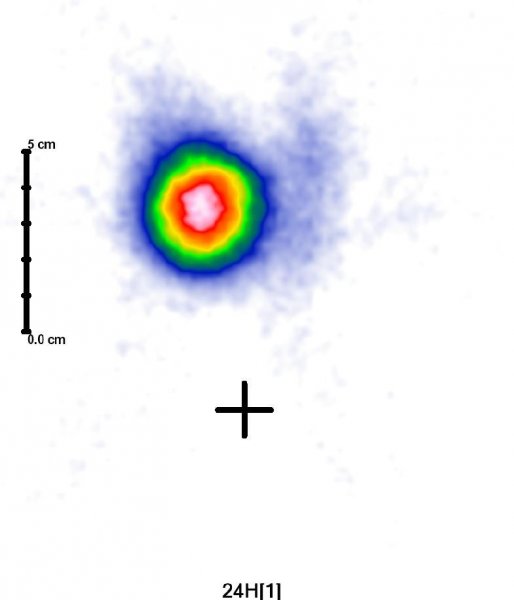

Przykładowe obrazy scyntygraficzne uzyskiwane w naszym Zakładzie Medycyny Nuklearnej: